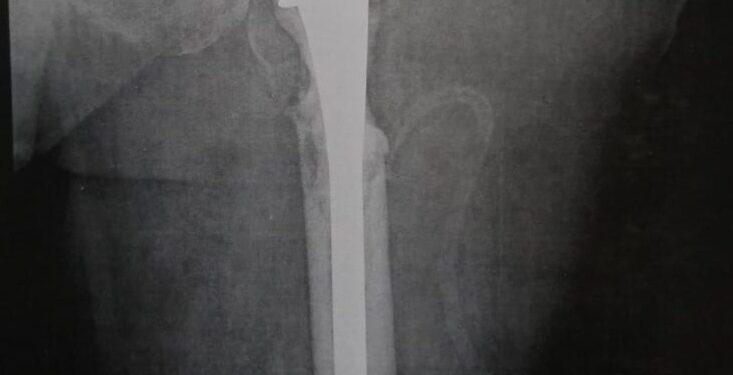

تم استقبال مريضة في منتصف الستينيات من عمرها تعاني من أورام سرطانية بالجسم أدت إلى ثانويات سرطانية بعظمة الفخذ أحدثت كسرًا مرضيا أعلى عظمة الفخذ وتأكل بالعظمة.

تم تحضير الحالة وعمل الفحوصات اللازمة، وخلال العملية الجراحية تم استئصال الورم واستبدال مفصل الفخذ بواسطة مفصل فخذ صناعي كامل أسمنتي طويل الجزع